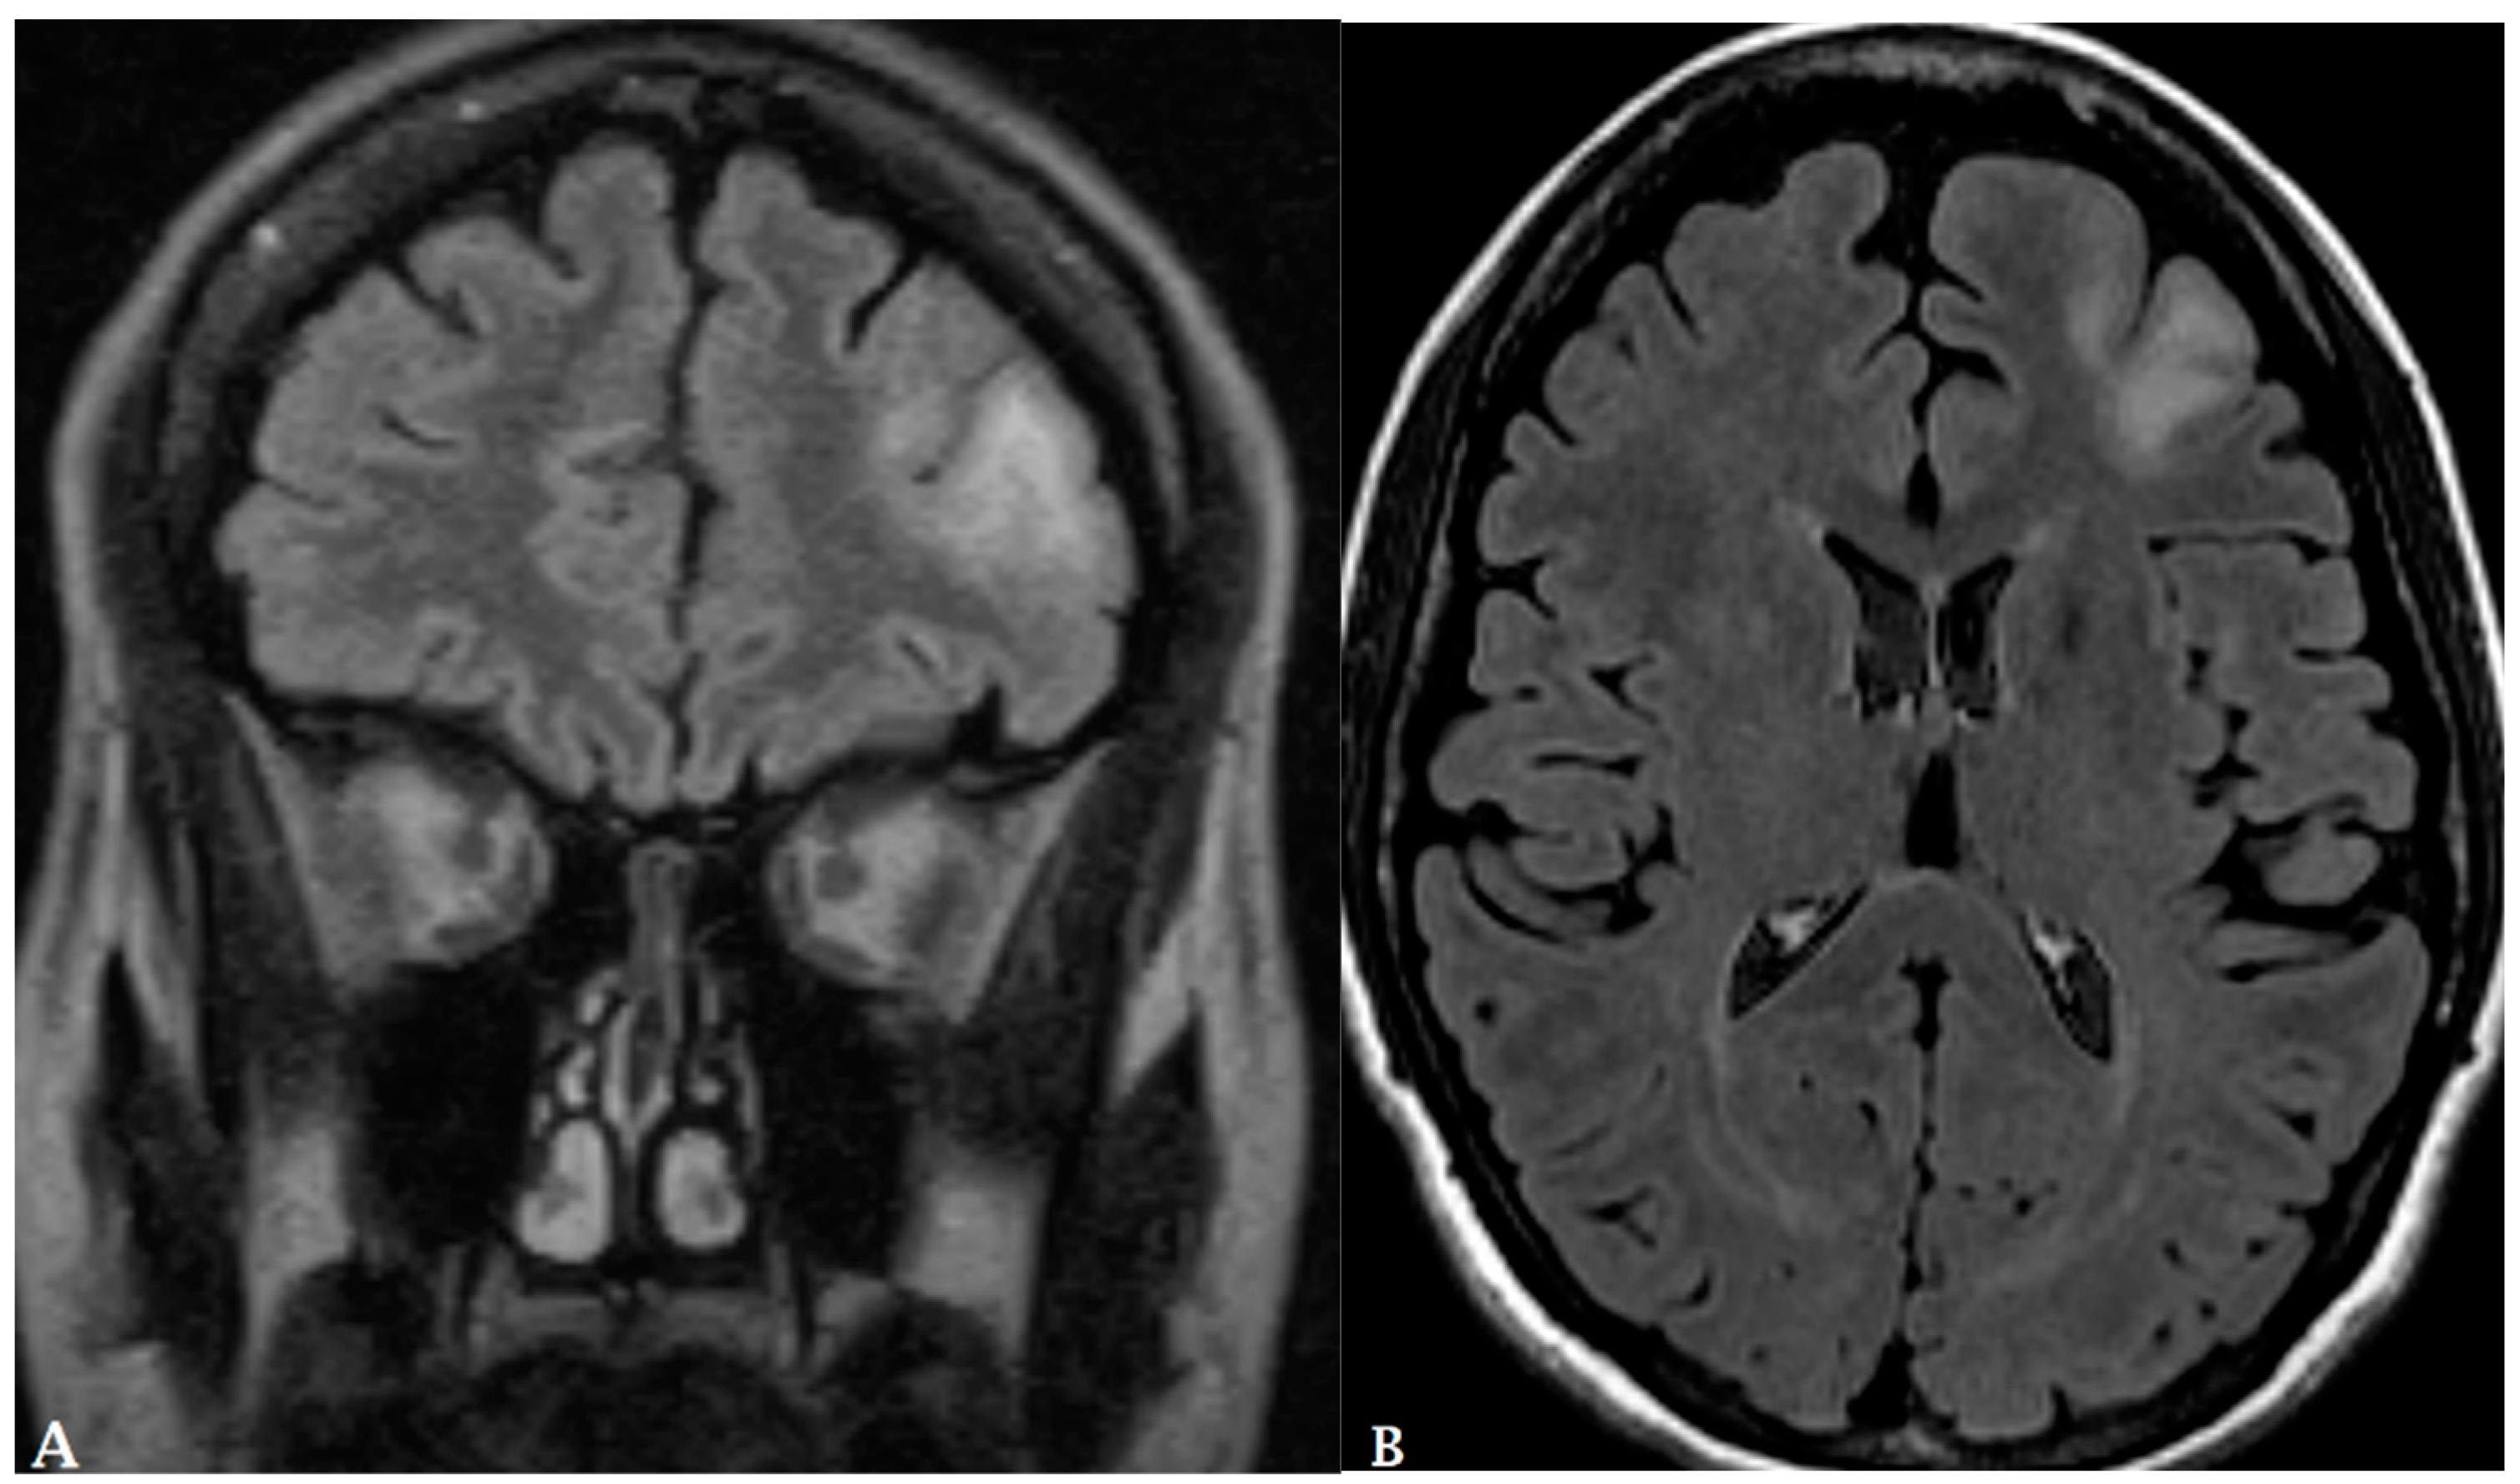

- Kang, D.; Park, J.E.; Kim, Y.-H.; Kim, J.H.; Oh, J.Y.; Kim, J.; Kim, Y.; Kim, S.T.; Kim, H.S. Diffusion radiomics as a diagnostic model for atypical manifestation of primary central nervous system lymphoma: Development and multicenter external validation. Neuro-Oncol. 2018, 20, 1251–1261. [Google Scholar] [CrossRef]